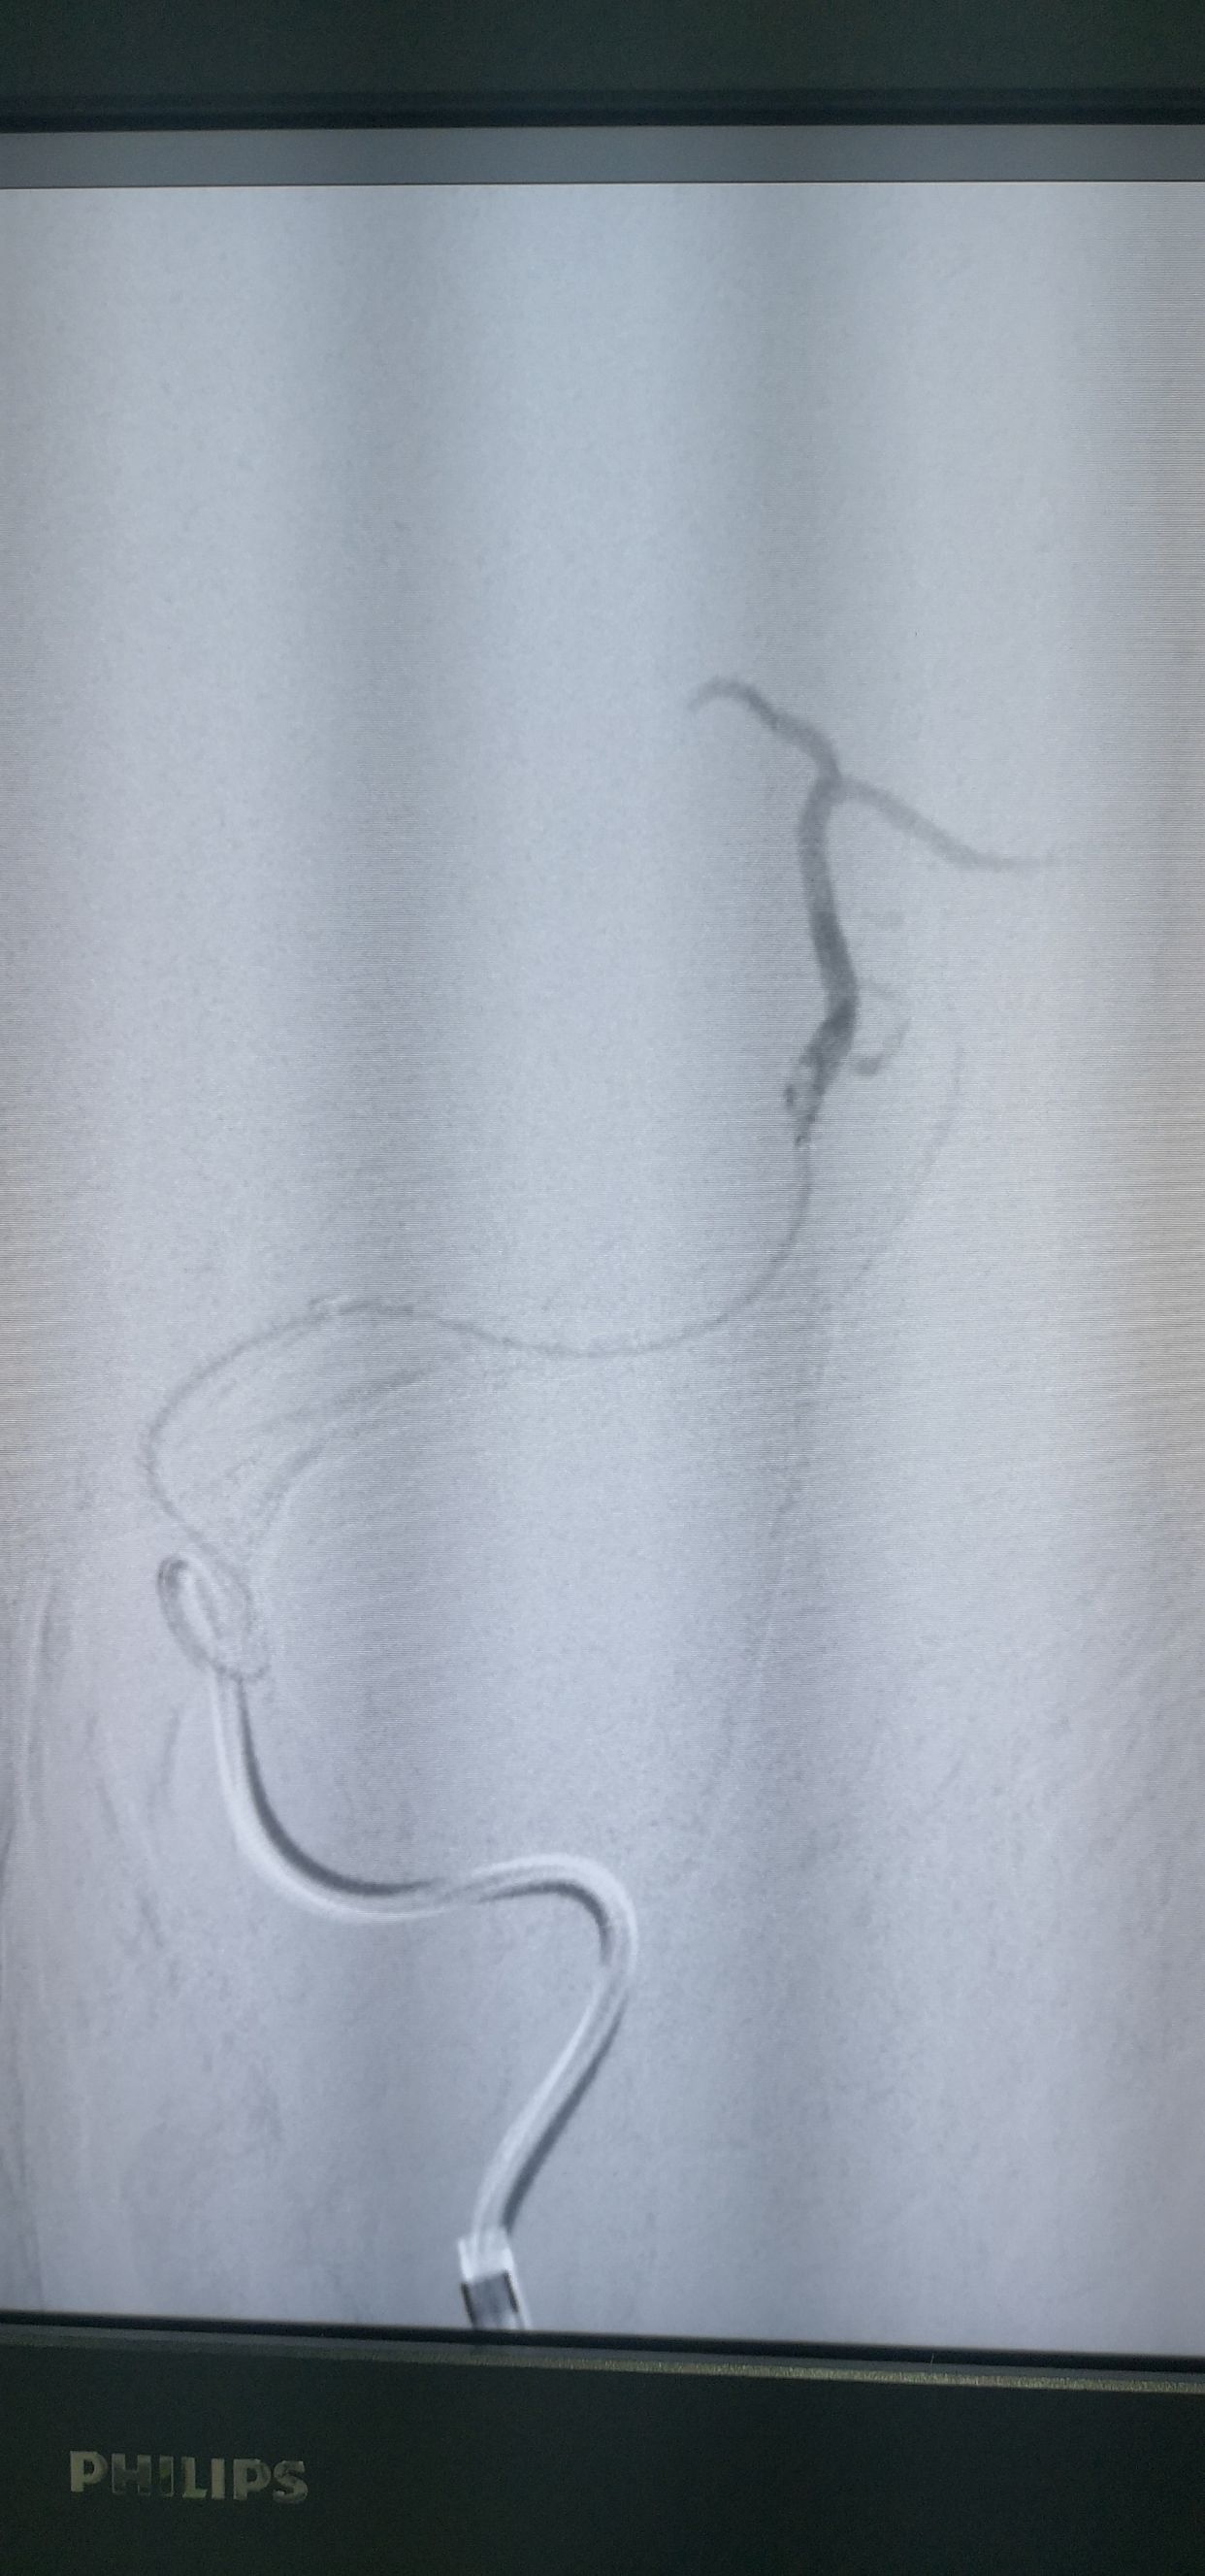

支架配合抽吸导管取栓

取出栓子